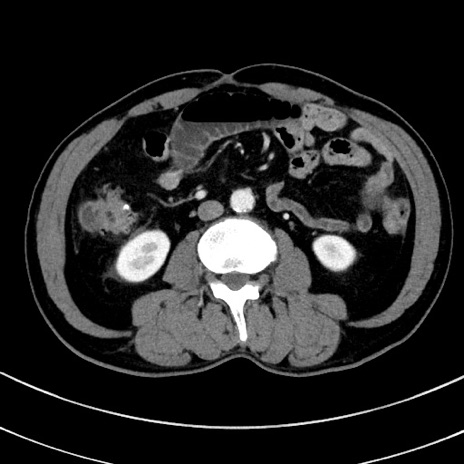

症例8(横断像)

【症例】 60歳代男性

【主訴】 黒色吐物

【現病歴】 4日前から嘔気自覚、2日前の朝食後にも嘔気あり、自分で手で嘔吐反射起こし嘔吐したところ血が混ざっていたため受診。

【既往歴】 5年前汎発性腹膜炎を伴う急性虫垂炎で手術、高血圧、前立腺肥大症、高脂血症

【身体所見】 腹部正中に手術癩痕あり 腹部平坦・軟圧痛なし膨満感あり

【データ】WBC 8400、CRP 4.54